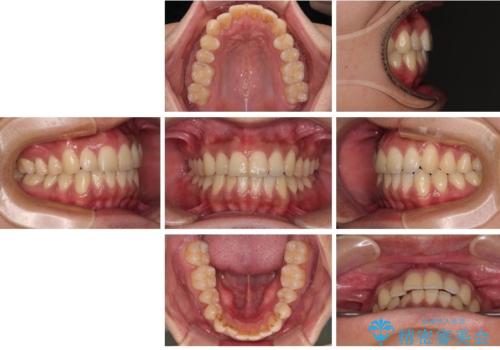

診察したところ、上下顎前歯部に軽度の叢生(ガタつき)が認められます。

目立たない装置を希望されたのでインビザライン ライトパッケージで治療を行うことになりました。